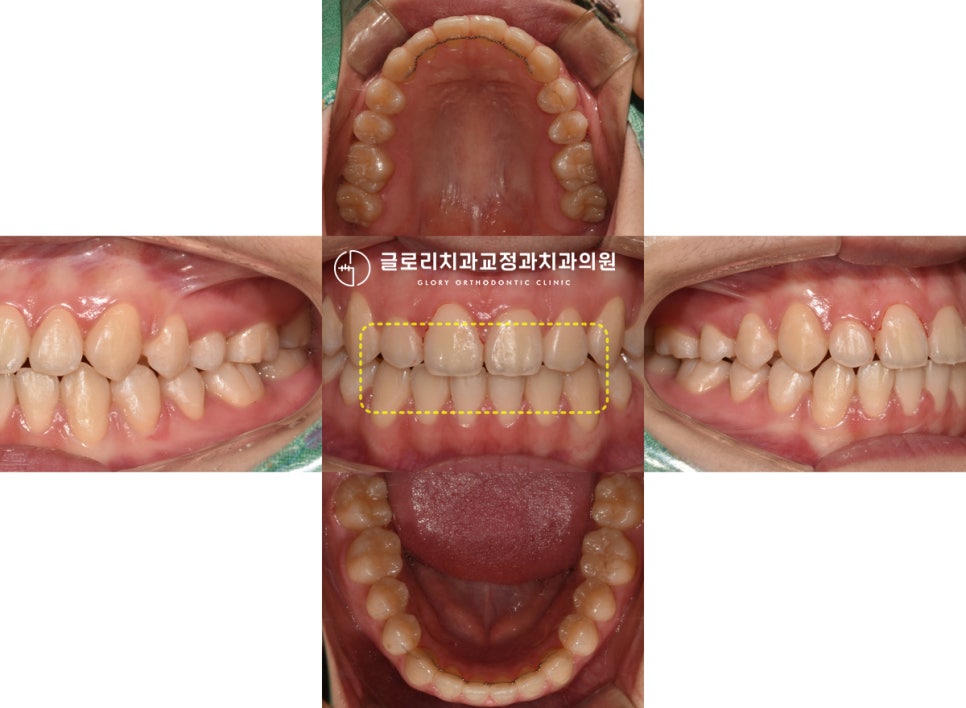

드디어 망우동치과 의 모든 과정이 끝났는데요

초진과 같은 곳을 표시해 놓았습니다ㅎㅎ

어떤가요? 훨씬 안정적인 모습을 보여주고 있죠?

배열도 더 고르게 바뀌었으며,

윗니가 아랫니

를 덮는 이상적인 모습이 되었네요.

몇 번 물어보시더니 너무 편하다며

말씀을 해주셨던 환자분,

끝으로 유지관리에 대한 중요성을

다시 한번 꼼꼼히 설명드리며 모든 과정을

마칠 수 있었습니다^^